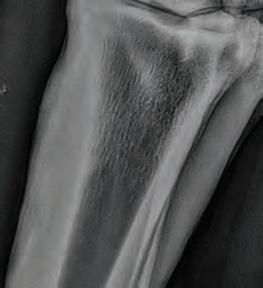

Bilateral hind cannon radiographs of X XXXX XXXXXX were taken on 14th April 21 and again 17th May 21 and 14th June 21. Initial radiographs showed a 32mm longitudinal non displaced left mid cannon saucer fracture extending 6mm into the dorsal cortex and a 44mm longitudinal displaced fracture right mid cannon 5.5mm in depth mid dorsal cortex associated proximally with a 27mm x 6.5mm secondary fracture (see right). Initially, surgical removal was recommended of the R H fracture fragment. A second series was taken on 17th May and third series on 14th June see right. Both fractures have attached and integrated with the parent bone with minor surface enthesophyte formation and periosteal activity evident.